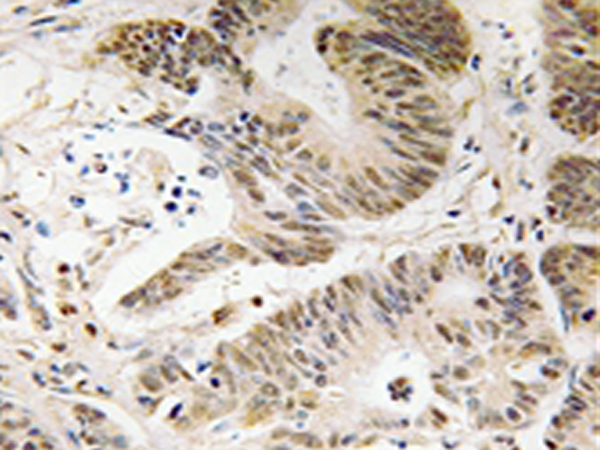

IHC |

IHC positive control: |

Human colon carcinoma tissue |

IHC Recommend dilution: |

50-100 |